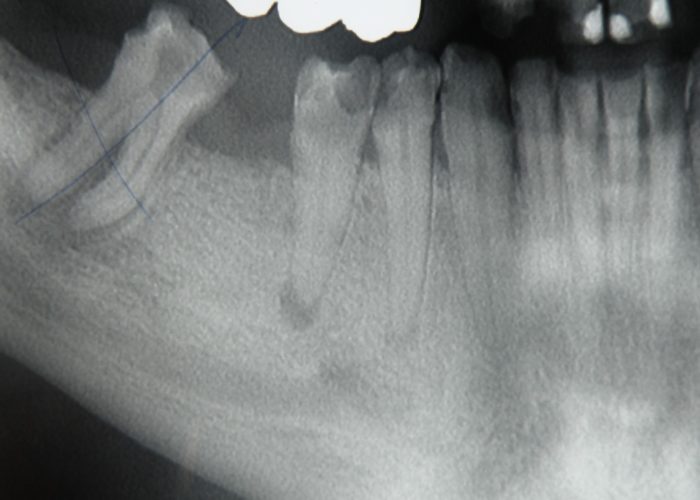

Liječenje granuloma

Liječenje granuloma u našoj se zubnoj ordinaciji vrši tradicionalnom metodom čišćenja zubnih kanala uz upotrebu lasera, koja garantira potpunu sterilnost očišćenih zubnih kanala.

U slučajevima koji zahtijevaju poseban pristup, ordinacija surađuje i sa specijalistom endodoncije.